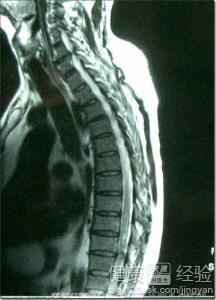

患有脊髓海绵状血管瘤应该如何正确治疗

同事在年底的时候被确诊为脊髓海绵状血管瘤,当时情况比较严重,不能自己排尿,双脚麻木基本上已经没有了知觉,站不起来。后来通过手术进行治疗,又加上一段时间的康复训练,在今年年初的时候就可以自己站起来了。有次和同事一起去他家探望,看到他已经可以慢慢行走,可以自行排尿了。感觉他恢复的很好,在和他以及他家人交流中也学到了一些关于脊髓海绵状血管瘤病症的知识,感觉很不错,在这里与大家分享一下,希望可以有所帮助。

2当诊断患有脊髓海绵状血管瘤时,特别是因为出血而造成的反复出现神经功能恶化的一些患者,是一定要坚持通过手术治疗的,手术一般都能安全的将脊髓海绵状血管畸形切除,效果比较好。再通过手术使脊髓出血除去后,浮肿现象会稍缓和,然后就要及时进行必要的内服治疗,促进脊髓出血陈旧化。

[需要做的检查]颅脑MRI检查、 血管造影